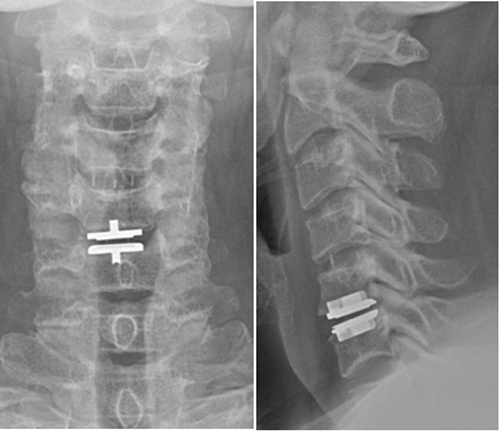

1.척추분리증으로 인한 척추전방전위증 환자의 수술전 사진

2.인공 디스크와 나사못을 이용한 척추유합술 및 후방 나사못 고정술로 척추분리증과 척추전방전위증이 교정된 상태